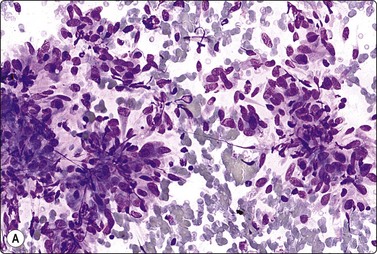

Merkel cell carcinoma (neuroendocrine carcinoma of skin) (Fig. 14.17, and see Fig. 5.23)61,62

image

Fig. 14.17 Merkel cell carcinoma

(A) Poorly cohesive cells; nuclear pleomorphism and some molding, scanty blue cytoplasm resembling lymphoid cells (MGG, HP); (B) Cellular smear of dispersed small cells with round, dark nuclei (Pap, HP); (C) Dot-like positive staining with CAM5.2 (immunostaining, HP).

Criteria for diagnosis

Cell-rich smears of mainly dispersed small neoplastic cells,

Fragile, scanty, blue (MGG) cytoplasm; high nuclear : cytoplasmic ratio; many stripped nuclei,

Clustered cells may show nuclear molding and rosette-like grouping,

Round or ovoid, mildly to moderately irregular hyperchromatic nuclei with inconspicuous nucleoli,

Mitoses frequent,

Lymphoid globules (lymphoglandular bodies) absent,

Dot-like paranuclear staining for cytokeratin; chromogranin usually positive.

Primary neuroendocrine carcinoma of skin is an uncommon neoplasm, mainly seen in elderly patients and most often in the head and neck. It is locally aggressive and often metastasizes to regional lymph nodes. Clinically and cytologically, Merkel cell tumor can be difficult to distinguish from non-Hodgkin lymphoma when it presents as lymphadenopathy without an obvious primary, as is often the case (see Chapter 5).

Page 379

Smears are usually highly cellular. The cells are mainly dispersed but some are clustered or form single files with nuclear molding and sometimes rosette-like groups. The main differential diagnoses are lymphoma and metastatic small cell carcinoma. Amelanotic melanoma may also be considered. The absence of lymphoid globules in the background and subtle differences in nuclear chromatin help in this distinction. Staining for CAM5.2, CK7 and CK20 demonstrates characteristic dot-like intracytoplasmic deposits in the tumor cells (Fig. 14.17C), and staining for neuroendocrine markers is usually positive. Electron microscopy shows well-demarcated whorls of cytoplasmic filaments.